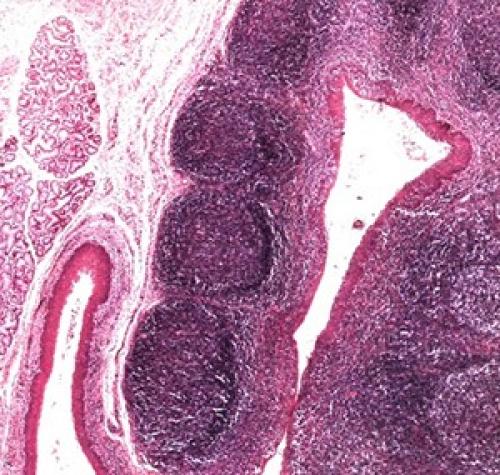

Небные миндалины представляют собой скопления лимфоидной ткани в глотке, их важной анатомической особенностью являются крипты. Крипты — это ветвящиеся углубления в миндалинах, благодаря которым увеличивается площадь соприкосновения лимфоидной ткани с инфекционными агентами и, как следствие, быстрее осуществляется иммунный ответ.

В криптах также образуются тонзиллолиты — казеозные пробки, представляющие собой плотные образования, состоящие из слущенного эпителия и остатков пищи. Обычно пробки мелкие и выводятся сами, для человека этот процесс протекает незаметно. В ряде случаев пробки задерживаются в криптах, а когда к ним присоединяются бактерии и лейкоциты, они увеличиваются в размерах и становятся более плотными. С наличием тонзиллолитов связывают ощущение дискомфорта в горле, першение, рефлекторный кашель и очень редко, лишь в 3% случаев — галитоз ( неприятный запах изо рта ). Среди нормальной микрофлоры крипт отдельно выделяются анаэробы, вырабатывающие летучие соединения серы, именно из-за них пробка приобретает характерный неприятный запах.

Дело в том, что нёбные миндалины (гланды) имеют внутри пустоты крипты, что увеличивает их эпителиальную поверхность (миндалина это лимфоэпителиальный орган). Эти крипты открываются на ротовую поверхность миндалины отверстиями- лакунами. Количество этих лакун вариабильно от одной до десятков. Не все лакуны самостоятельно можно обозреть, так как некоторые могут быть прикрыты дубликатурой передней нёбной дужки, так называемой складкой Гиса, которая может усложнять эвакуацию патологического содержимого.

Пробки в горле это продукт воспалительного процесса в нёбных миндалинах, гнойные пробки в горле представляют собой десквамированный эпителий, мёртвые лейкоциты, скопление гнилостных микробов. Нёбная миндалина очень рефлексогенная зона имеющая в своей толще множество нервных окончаний, пробки в горле оказывают раздражающее действие на эти окончания что обуславливает ряд жалоб предъявляемыми больными хроническим тонзиллитом.